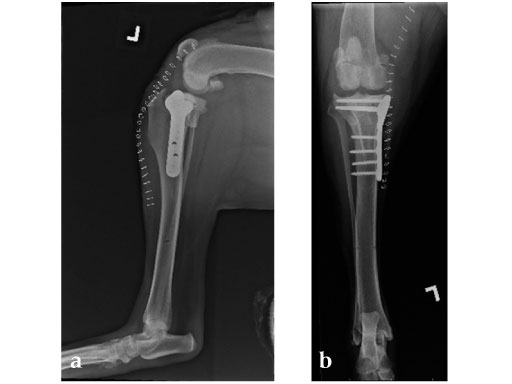

Case 3: Eight-year-old Australian cattle dog

(Case provided by Brian Beale, Houston, USA)

An 8-year-old, female, spayed, 24 kg Australian cattle dog. This breed has short stocky legs and is very energetic and strong. The added strength of the 3.5 mm plate over the TPLO 2.7 mm plate was an advantage. The smaller head profile and shorter length of the TPLO 3.5 mm small stature plate allowed it to fit nicely on this patient.